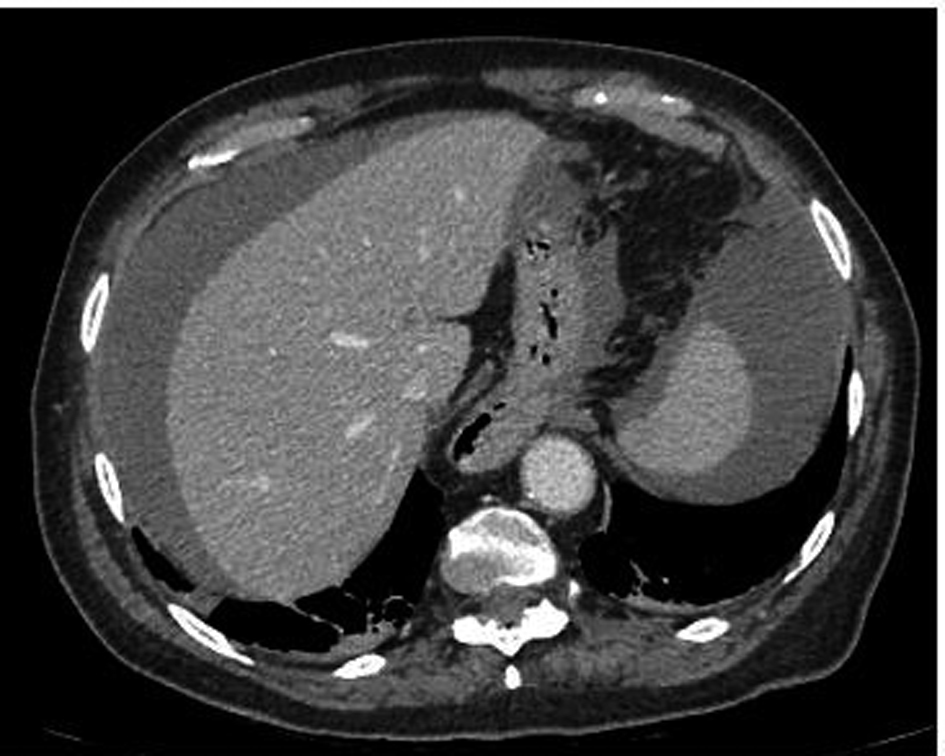

On examination by the general surgical team, she was afebrile with a blood pressure of 180/92 mmHg and a pulse rate of 70 per minute. There was demonstrable abdominal tenderness particularly in the epigastric area but without guarding. The SPC was draining clear urine but there was a small amount of blood leaking from around the insertion site. An abdominal CT scan was requested. Whilst waiting for the CT scan, she had two hypotensive episodes that responded to fluid resuscitation. The CT scan showed the SPC to be in situ and presence of high-density fluid within the abdomen and pelvis in keeping with haemorrhage (Fig. 1).

![]() Click for large image | Figure 1. CT abdomen showing blood surrounding liver and spleen. |

EP was given Beriplex® (prothrombin complex concentrate) to reverse her INR. At emergency laparotomy, an injury to the small bowel was identified with a large haematoma in the mesentery and approximately 2400 mL of blood with clots in the peritoneal cavity. A small bowel resection with end to end anastomosis was performed. Post operatively she required intensive care for ongoing cardiovascular support in the form of close fluid balance and inotropic support in the intensive therapy unit. Her post operative recovery was complicated by confusion, generalised weakness and sepsis of unknown source. She gradually improved in all areas and 26 days later was discharged to a community hospital for 15 days of further rehabilitation.